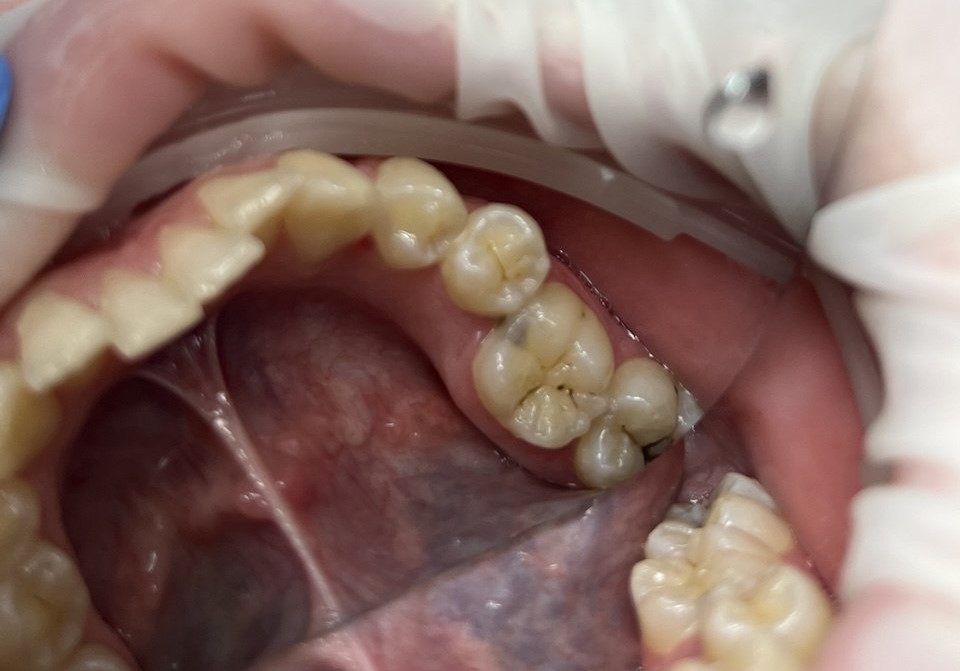

На 37 зубе выявлен кариес средней глубины. Провели обезболивание, изоляцию, полное удаление поражённых тканей и контроль маркером. Полость восстановлена эстетичным композитом Estelite, что позволило вернуть правильную форму бугров и плотный межзубной контакт. Завершили лечение шлифовкой и полировкой.